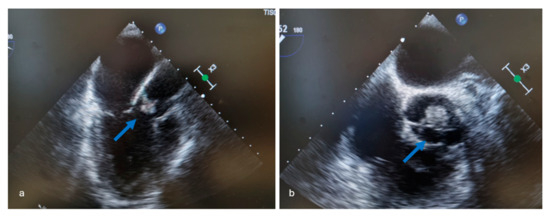

- vegetation